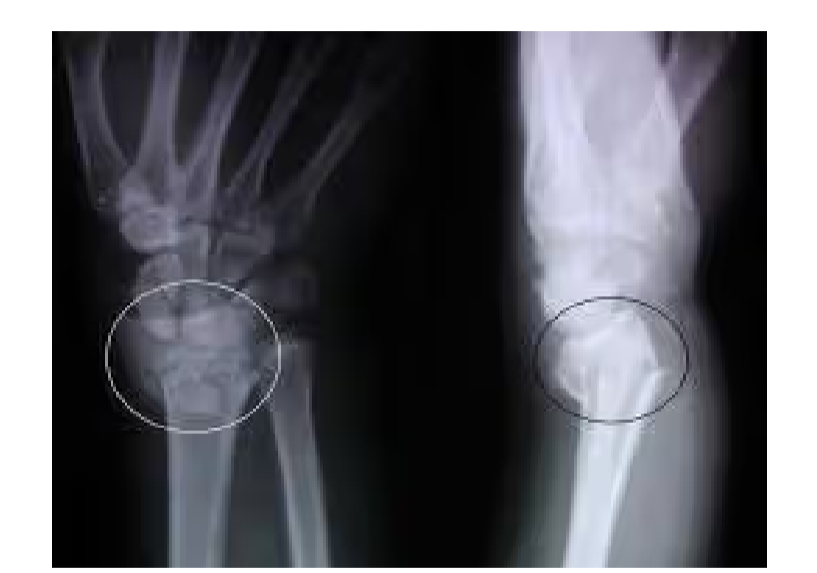

What is this?

Colles fracture

Smith fracture